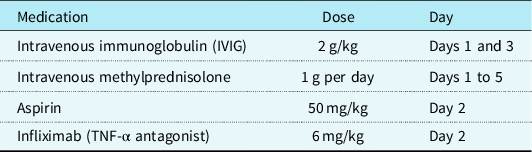

In view of the hyperinflammatory clinical picture, and after multidisciplinary team discussion, the patient was treated with immunomodulation therapy in the form of intravenous immunoglobulin 2 g/kg on days 1 and 3, intravenous methylprednisolone 1 g per day on days 1–5, aspirin 50 mg/kg on day 2, and infliximab (TNF-α antagonist) 6 mg/kg on day 2 (Table 2). Infliximab was chosen for its evidence-based role in refractory Kawasaki disease. Reference Dionne, Burns and Dahdah2 A full course of clindamycin and ceftriaxone antibiotics was also completed.

Table 2. Immunomodulation therapy